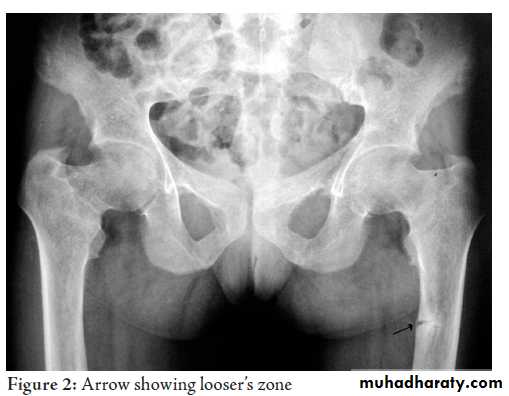

3-Renal disease.In osteomalacia the features are

. loss of bone density.Thinning of the trabeculae and the cortex

.looser zones

.bone deformity vertebral bodies are biconcave , the femora may be bowed & in severe cases the side walls of the pelvis may bend inwards , giving to the so called triradiate pelvis .